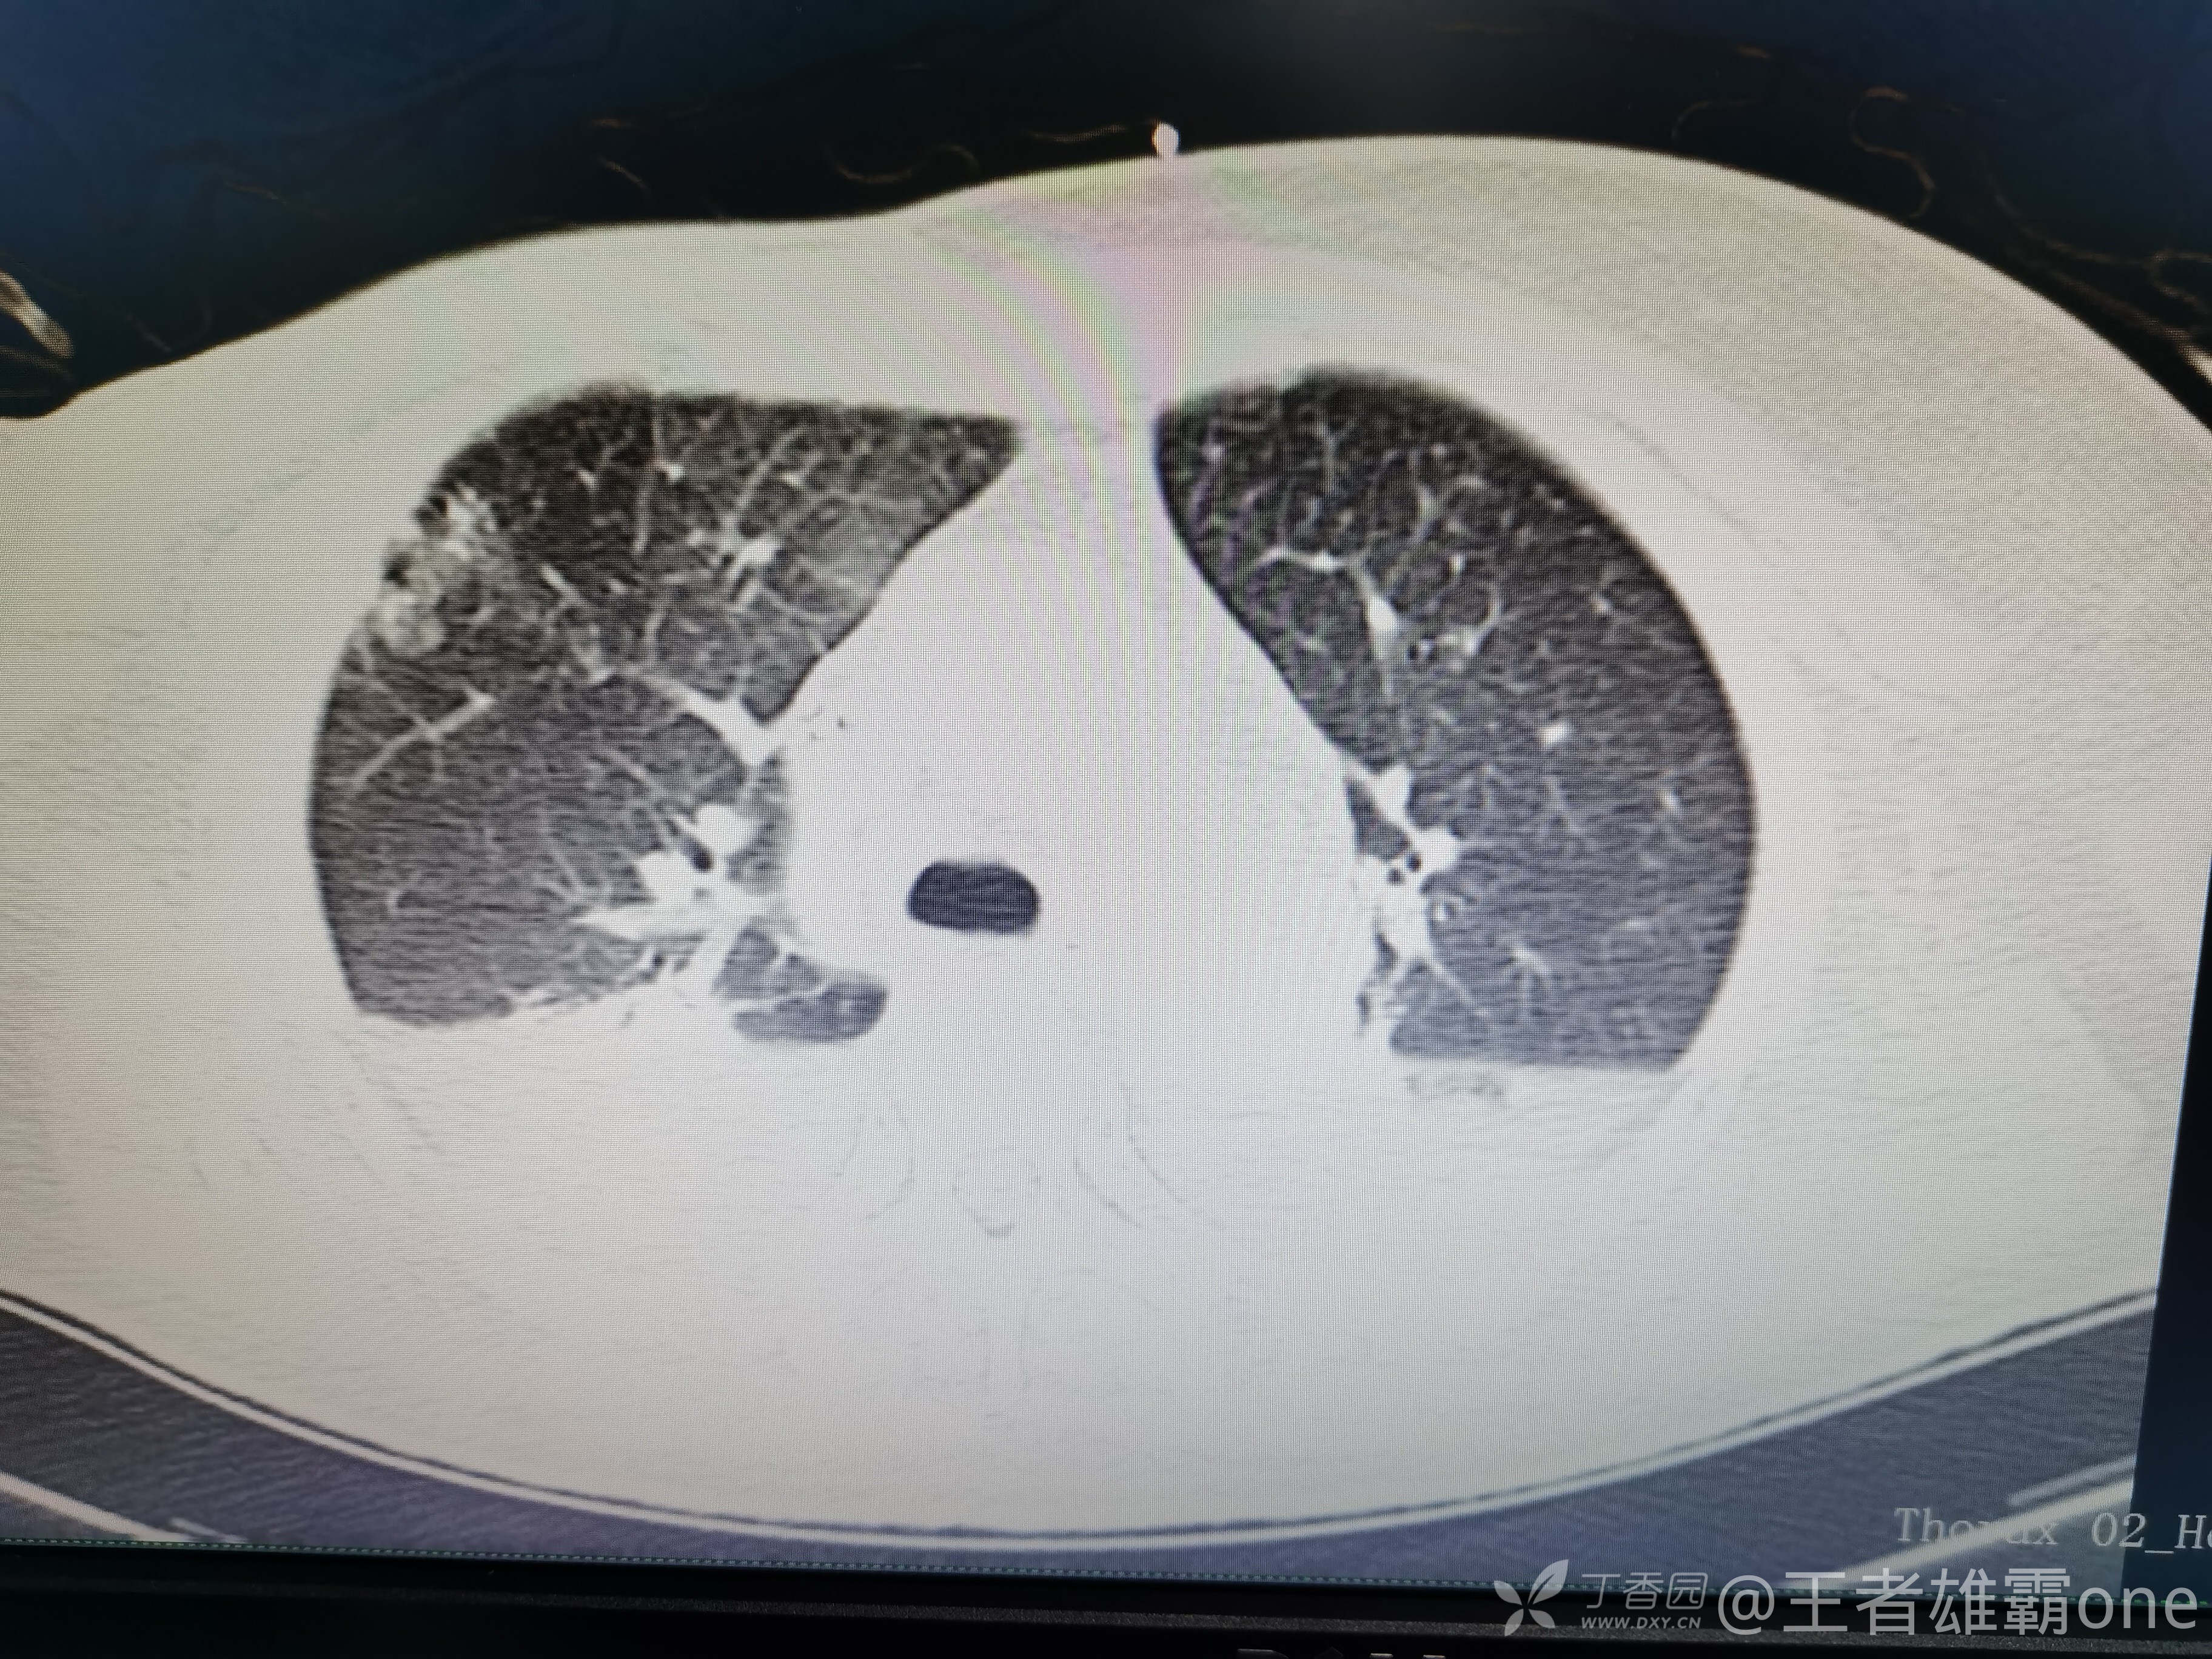

早上复查血常规:血红蛋白100g/L,白细胞11.1×109/L,血小板29×109/L。凝血功能:APTT37.9s,纤维蛋白原3.01g/L,凝血酶时间18.6s,D二聚体21530ug/L。生化:白蛋白36.2g/L,胆红素指标正常,谷丙56U/L,总胆红素38mmol/L,直接胆红素12.1mmol/L,谷草57U/L,肌酐91.1ummol/L,尿素13.97mmol/L,超敏C反应蛋白142.1mg/L。降钙素原17.70ng/ml。脑钠肽前体2164pg/ml。复查胸部CT:

那么问题来了,出现呼吸衰竭气管插管的病因是?请大家讨论分析!